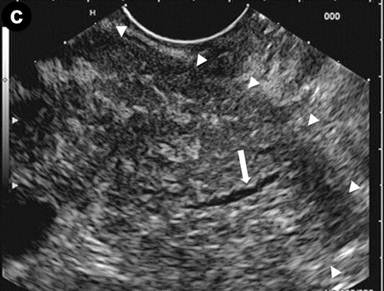

A 24-year-old man presenting with jaundice and elevated levels of IgG4 (366 mg/dL; reference range: 8-140 mg/dL). Magnetic resonance cholangiopancreatography (MRCP) was requested; the T2-weighted coronal scan (Image 1a) showed dilated intra- and extra-hepatic bile ducts with an abrupt stricture (arrow) of the intrapancreatic common bile duct; the pancreatic duct was narrowed throughout its course. Subsequent EUS (Image 1bc) revealed a diffusely and substantially enlarged pancreatic gland (arrowheads) with echopoor echotexture and a normal main pancreatic duct having a diameter of 1.3 mm (Image 1b, arrow), measured with calipers (Image 1c, arrow). Hyperechoic septa were well visible in the enlarged gland. Stenosis of the distal bile duct was due to a diffuse thickening of the wall with an intermediate echopoor layer, and echorich outer and inner layers ("sandwich-pattern") (Image 1d, arrowheads).